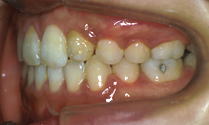

この方のかみ合わせです。

→

単純にすき間を閉じるだけでなく、かみ合わせも整いました。